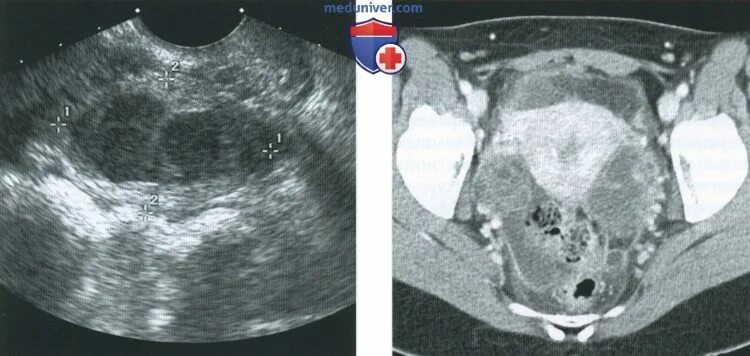

Pyosalpinx латынь